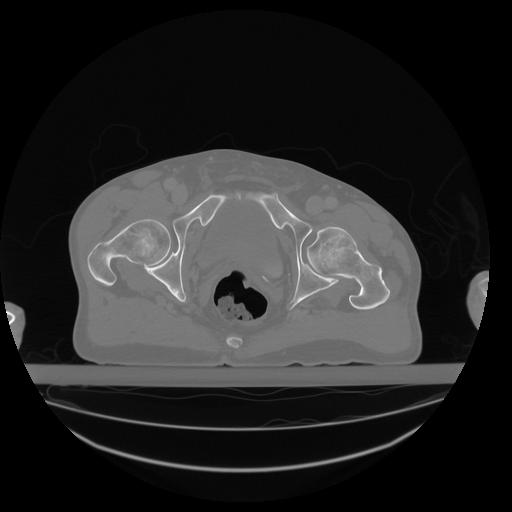

34 CUERPO,CE,Vol,1.0,CUERPO,,